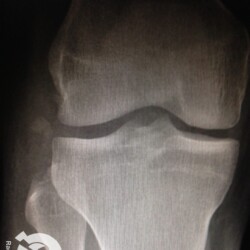

Fratura da patela com importante desvio e fratura cominutiva do 1/3 proximal da tíbia comprometendo a eminência intercondiliana.